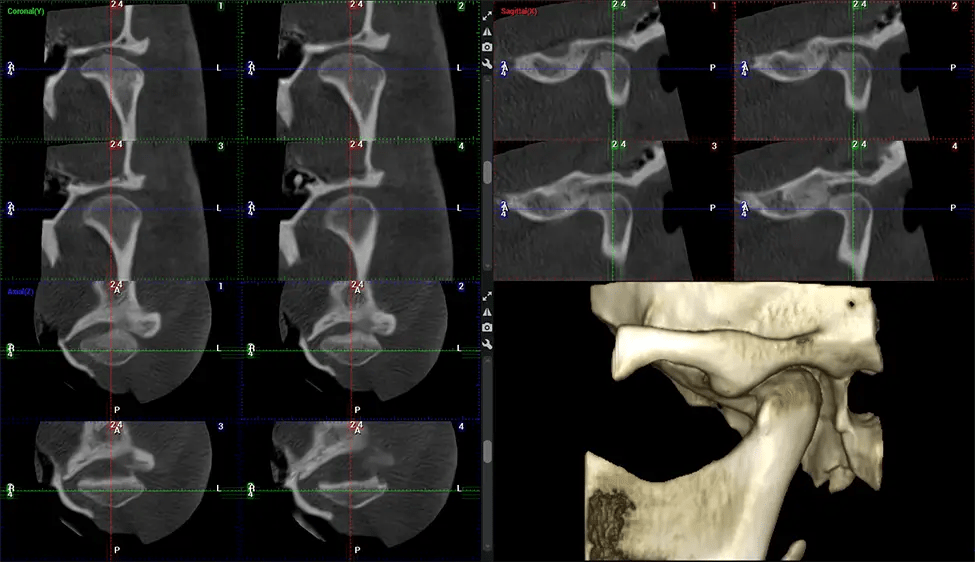

Cone Beam Computed Tomography (CBCT) is an advanced imaging technique used in dentistry and maxillofacial surgery to obtain detailed 3D images of the oral and maxillofacial structures. At Dr G Dental Studio, our CBCT scanners utilize a cone-shaped X-ray beam and a specialized detector to capture images from different angles. A computer then combines these images to create a 3D representation of the patient’s oral anatomy.

This 3D scan, called cone beam computed tomography, gives your dentist a more complete image of your oral anatomy and disease processes than a traditional X-ray. Unlike conventional X-rays, which capture a 2D image of your mouth from various angles, a 3D scan takes multiple digital X-rays for one image. It provides a complete view of your jaw, teeth, nerves, and soft tissues. This enhanced view allows dentists to detect minor issues not visible in traditional 2D scans, such as impacted wisdom teeth or bone fractures in the sinus cavity.

The patient is first positioned in the CBCT scanner, which typically consists of a rotating arm that houses the X-ray source and a detector. The patient’s head is immobilized to ensure accurate image capture. The X-ray source and detector rotate around the patient’s head, capturing various X-ray images from multiple angles. As the X-ray source rotates, it emits the cone-shaped X-ray beam towards the detector. The detector captures the X-ray images, which are then processed by the CBCT software.

After the scanning process, the captured X-ray images are processed by the CBCT software, which applies algorithms to reconstruct a detailed 3D image of the scanned area. The software compiles these individual X-ray images and creates a digital 3D representation of the patient’s anatomy. The reconstructed 3D CBCT image can be viewed and analyzed by the dentist or radiologist. This image can be manipulated, rotated, and zoomed in or out to examine specific structures and evaluate the patient’s condition.